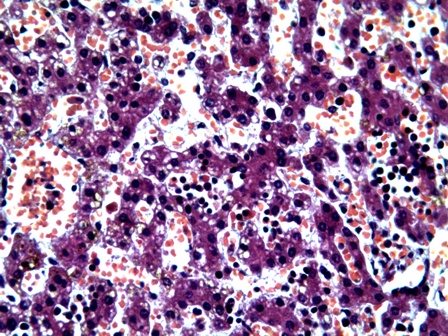

более выраженным (рис. №1). Во всех случаях имели место очаги

экстрамедуллярного кроветворения в печени, которые рассматривались как признаки морфологической незрелости ткани

вследствие внутриутробной гипоксии плода (рис. №2). Кроме этого отмечалось увеличение объема стромальных компонентов миокарда

Рисунок

1- Очаги

экстрамедуллярного кроветворения в ткани печени

3. Маркерами тканевой

внутриутробной гипоксии явились глиоз

субэпендимарной и стволовой части мозга, очаги экстрамедуллярного кроветворения

в ткани печени, увеличение объема стромальных компонентов миокарда желудочков

сердца и утолщение стенок легочных

артериол вследствие гиперплазии мышечного слоя